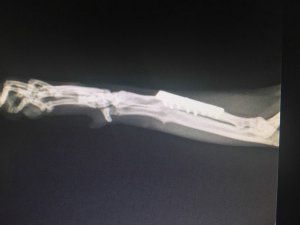

Gute Nachrichten. Jokers Platte kann vorerst drin bleiben. Auf dem Röntgenbild sieht alles sehr gut aus. Die Fraktur, die er sich zusätzlich unter der Platte zugezogen hatte, ist einwandfrei verheilt. Der Knochen über der Platte wächst schön gerade. Ich soll nur darauf achten, ob Jokers Körper die Platte nicht doch irgendwann abstößt, dann muss sie natürlich raus. Aber bis dahin heißt es Gott sei Dank „keine Boxenhaft für den kleinen Racker“.

Genau so hatte ich mir das gewünscht. Nach Fund und Operation hatte Joker Probleme, auch mit

Giardien. Ein längerer stationärer Aufenthalt war darum erforderlich. Ich hatte Sorge, dass die bei einer erneut nötigen Op und dem damit verbundenen Stress wieder auftreten könnten. Darum soll er auch weiter auf der Pflegestelle mit seinen beiden Onkels Bobby und Sammy leben.